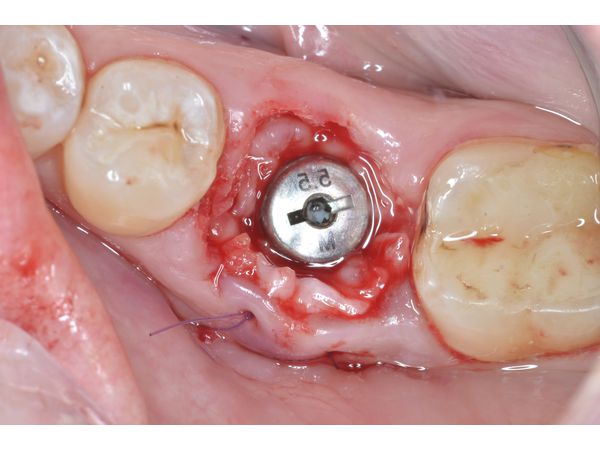

4. Произведён забор трансплантата с бугра верхней челюсти, его подсадка с вестибулярной стороны, после чего трансплантат фиксирован швами Monosyn 5.0 (увеличение объёма мягких тканей),уложен костный материал Bioss L, а также установлен формирователь десны.